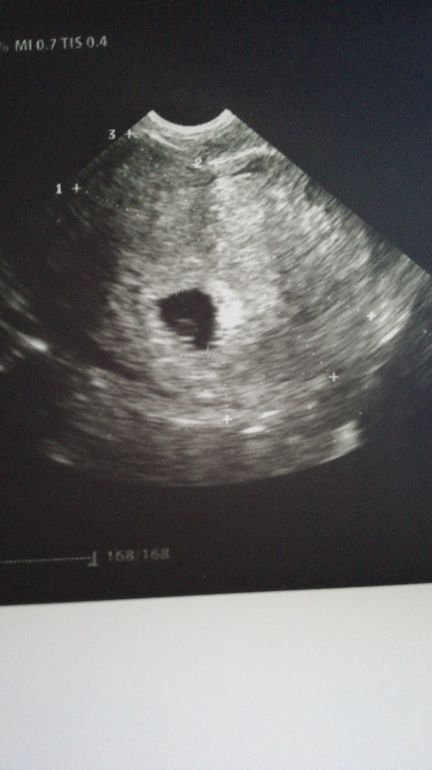

Уже такой срок). Вчера была на УЗИ и у гинеколога. Пя 1,4, желточный мешочек 0,5, эмбрион ещё не визуализировать. Гинеколог поздравила, назначила анализы, завтра еду сдавать, 30 на прием, будет брать мазочки. Дюфастон сказала буду точно принимать до 16 недель. Сейчас пока вит.Е, фольку и хофитол по 2т*3р.д. А по самочувствию- мутит, почти постоянно. Начала чувствовать как растет матка, это из-за варикозное сильного. УЗИ переделать через неделю.

Маленький, а уже видно что красивенький (-ая) 😊😉

По мне уже эмбриончик закладывается😍растите и пусть вас по скорее найдут)

Растите! По-моему зачатки эмбриоши уже видно)